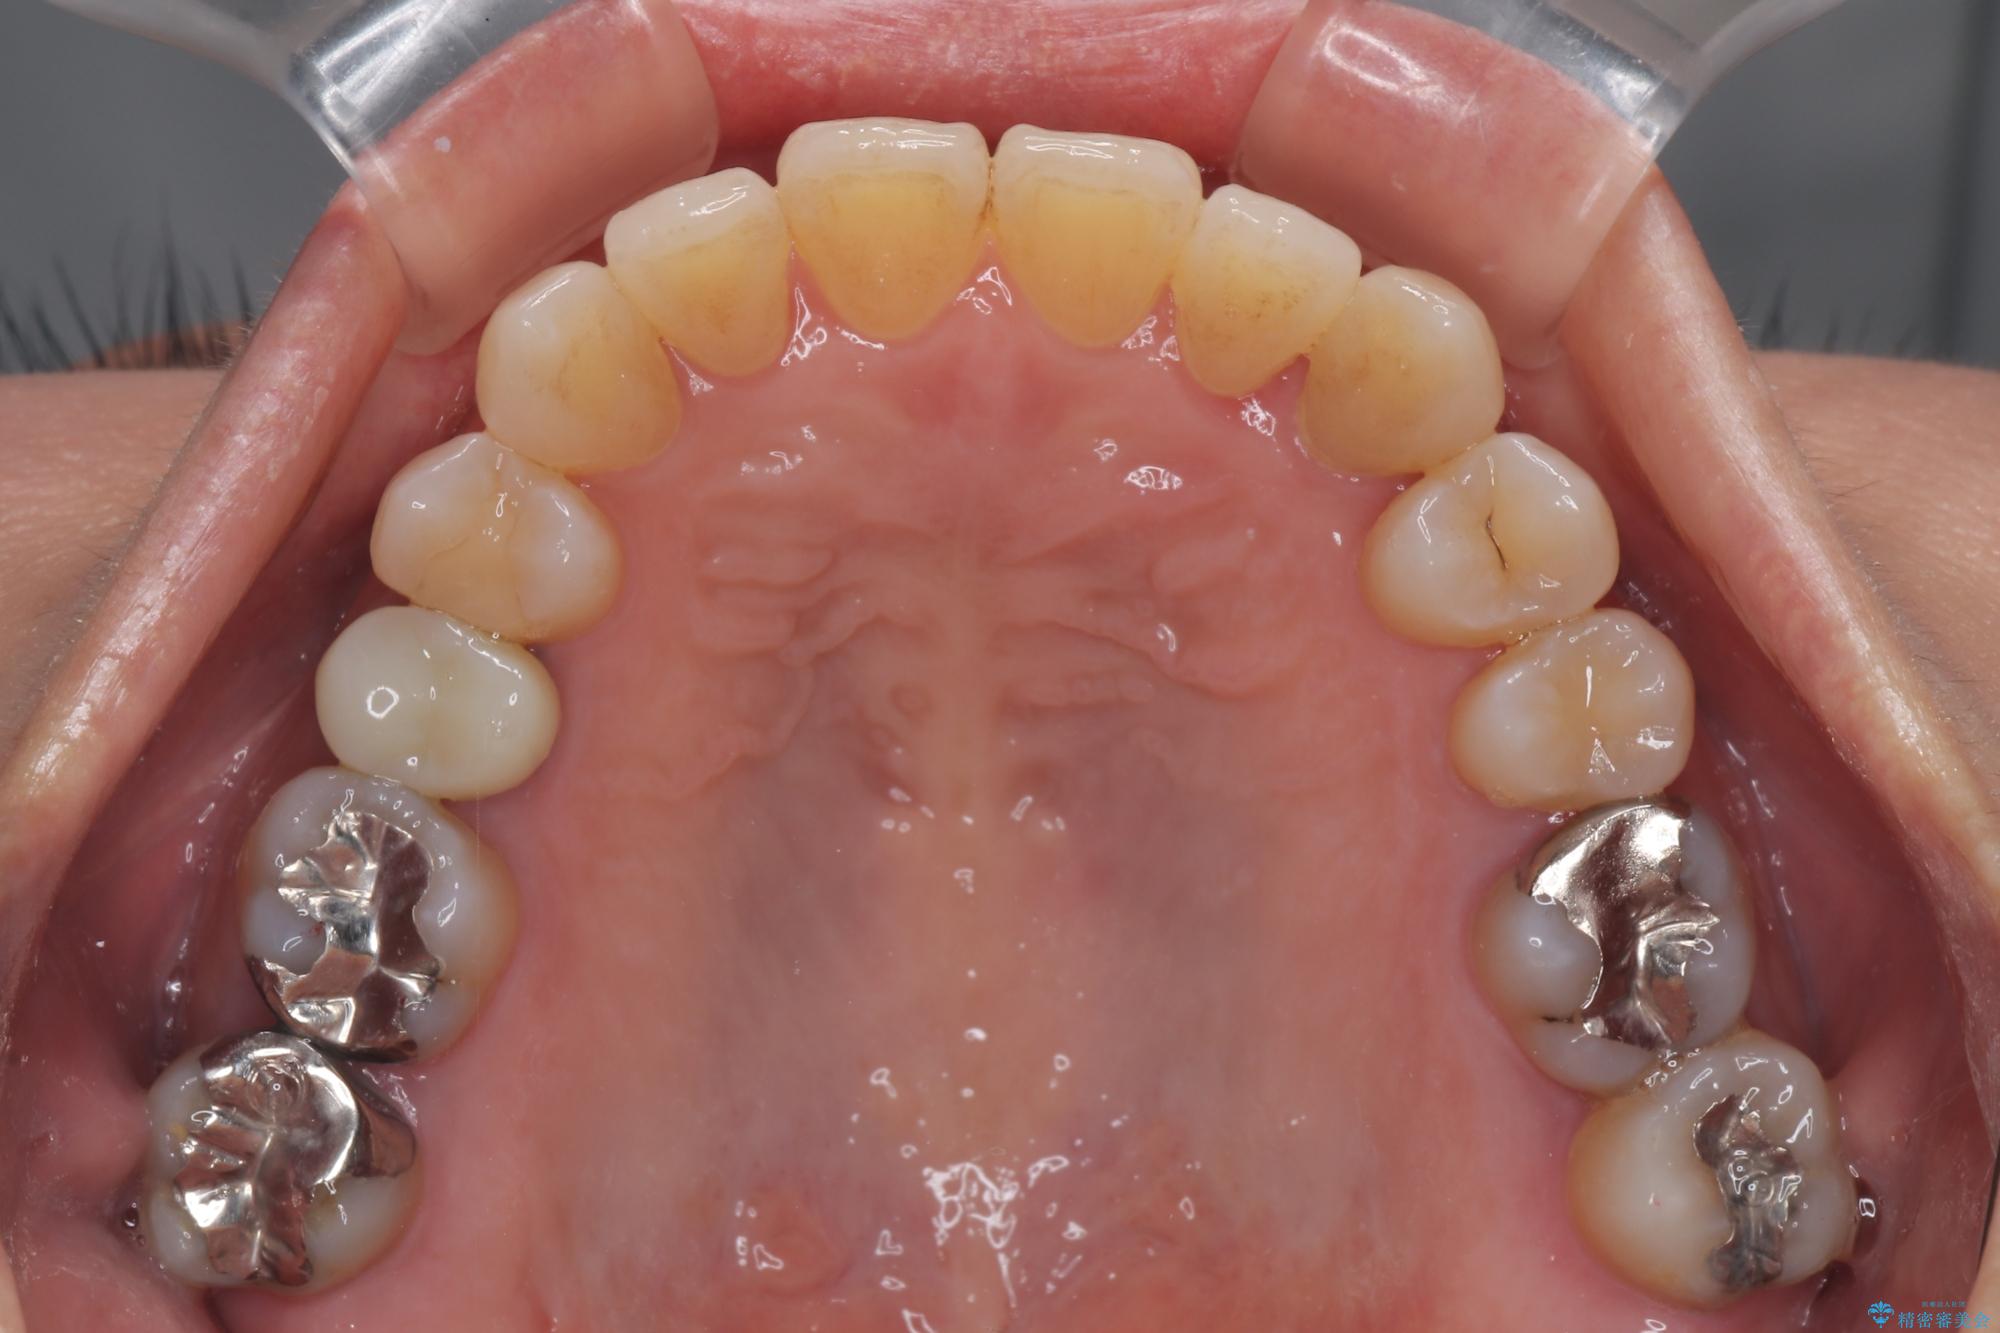

- 前歯のデコボコや八重歯を治したいとのことで来院された患者様です。

受け口傾向の骨格であり、前歯はクロスバイトまたは切端咬合となっており、下顎を中心に歯列全体の後方移動を行い、IPR(歯と歯の間を削る)によってデコボコが解消するように設計し、インビザラインにより治療を行うこととしました。

受け口傾向のインビザライン矯正は比較的治療を行いやすいため、きれいに仕上げることができました。舌の突出癖が顕著であったため、改善のためのトレーニングをしっかりと行っていただきました。